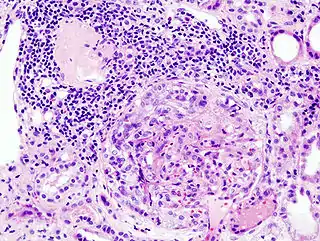

![]() Imagen histopatológica de una muestra de glomerulonefritis con semilunas obtenida de un paciente con glomerulonefritis rápidamente progresiva positiva para anticuerpos anti-MPO-ANCA. Tinción con hematoxilina y eosina. | ||

El primer paso es el ataque inmunitario de la membrana basal glomerular con aparición de auténticos "orificios" a través de los cuales van a pasar distintos componentes de la sangre que luego ingresarán al espacio de Bowman. Diversos factores plasmáticos, entre los que se destaca la fibrina, actuarán como el estímulo quimiotáctico y proliferativo que dará lugar a la formación de las semilunas. Esta evolución tan característica determina las diferentes morfologías de las semilunas, que según los estudios con microscopia óptica son celulares, fibrocelulares o fibrosas. El resultado final es la evolución a un cuadro de fibrosis progresiva y esclerosis glomerular.[13] De acuerdo con lo informado por los autores de varios trabajos en este proceso intervienen moléculas de adhesión celular, interleucinas, integrinas y factores de crecimiento.[14]

Pese a la gran variedad de enfermedades que causan glomerulonefritis rápidamente progresiva, todos los tipos se caracterizan por daño glomerular y formación de semilunas. El daño más grave y la ruptura de la membrana basal glomerular conducen a la pérdida de proteínas plasmáticas. De estas proteínas, se piensa que la fibrina es la que más contribuye a la formación de semilunas. Las células epiteliales que delimitan la cápsula de Bowman responden al estímulo proliferante de la fibrina. También puede haber infiltración de leucocitos como los monocitos y los macrófagos, los que también pueden proliferar bajo la influencia de la fibrina. Estas células proliferantes rodean al glomérulo y lo comprimen por lo que aparece la cicatriz con forma de semiluna que es visible con el microscopio en el material obtenido de una biopsia renal.[2]

Anatomía patológica

En la biopsia de estos pacientes se halla una importante proliferación de las células epiteliales de la cápsula de Bowman, con formación de semilunas en los glomérulos.[4] La biopsia renal confirma la presencia de una glomerulonefritis con semilunas epiteliales. Entre las características histopatológicas figura la infiltración del espacio urinario por células mononucleares asociada con la proliferación del epitelio parietal de la cápsula de Bowman o la proliferación extracapilar con formación de semilunas que pueden afectar del treinta al cien por ciento de los glomérulos. En estos se ve un engrosamiento de la cápsula de Bowman con formación de semilunas. También puede haber fibrosis parcial y sinequia del penacho glomerular a la cápsula.[4] Las semilunas, que pueden ser segmentarias o circunferenciales, ocupan todo el espacio de Bowman y ahogan el ovillo capilar, según el estado evolutivo pueden clasificarse en celulares, fibrocelulares o fibrosas y representan fases progresivas del mismo proceso.[4] En la glomerulonefritis rápidamente progresiva de tipo I hay positividad lineal sobre todo para IgG pero después también para C3. Dos tercios de las glomerulonefritis semilunares de este tipo corresponden al síndrome de Goodpasture y el otro tercio carece de manifestaciones pulmonares (síndrome de Goodpasture sin compromiso pulmonar). La lesión glomerular es similar en ambos grupos y se produce por un mecanismo inmunitario antimembrana basal glomerular. Como ya se dijo, el factor desencadenante es un defecto de un componente proteico de la cadena α3 del colágeno de tipo IV.[5] En la enfermedad de tipo II hay positividad granular o nodular o de ambas formas, difusa y global, debido a depósitos de complejos inmunes que con el microscopio electrónico se ven como depósitos densos. Este tipo por lo general corresponde a variedades de la glomerulonefritis aguda difusa, de la glomerulonefritis mesangiocapilar y, menos a menudo, de la enfermedad de Berger.[5]

Por último, en la glomerulonefritis semilunar de tipo III el examen con inmunofluorescencia es negativo y los hallazgos detectados con el microscopio electrónico son similares a los de la enfermedad de tipo I (sin depósitos densos). Si bien se ignora la patogenia de esta lesión glomerular, se piensa que en una buena cantidad de casos la causa de la ruptura de capilares glomerulares y de la proliferación celular glomérulo-capsular sería una vasculitis o una angiopatía. Este cuadro se observa con mayor frecuencia en adultos mayores.[5]